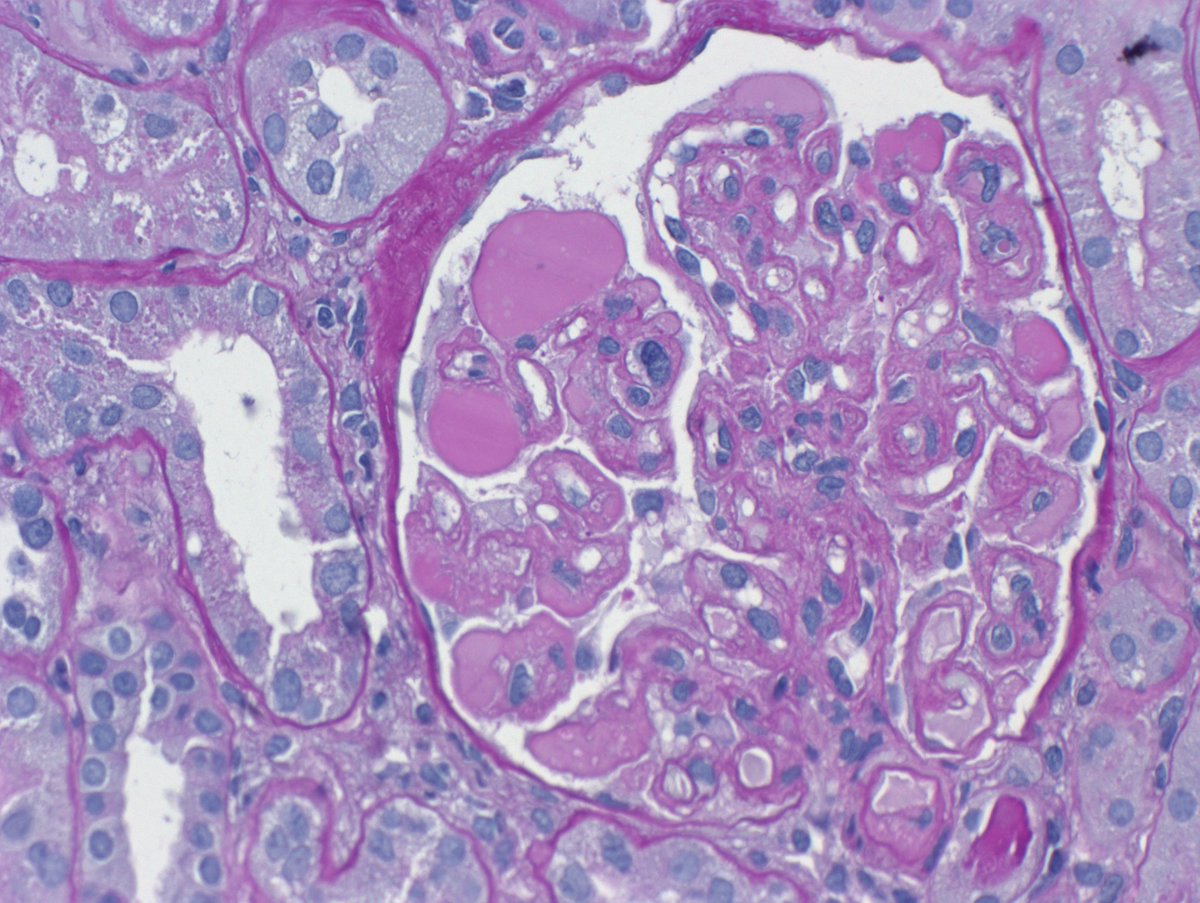

Long weekend often brings urgent cases. Here is one that was STATed, ended up showing anti-GBM GN. Diffuse crescents (nearly 100%). Linear IgG. #RenalPath